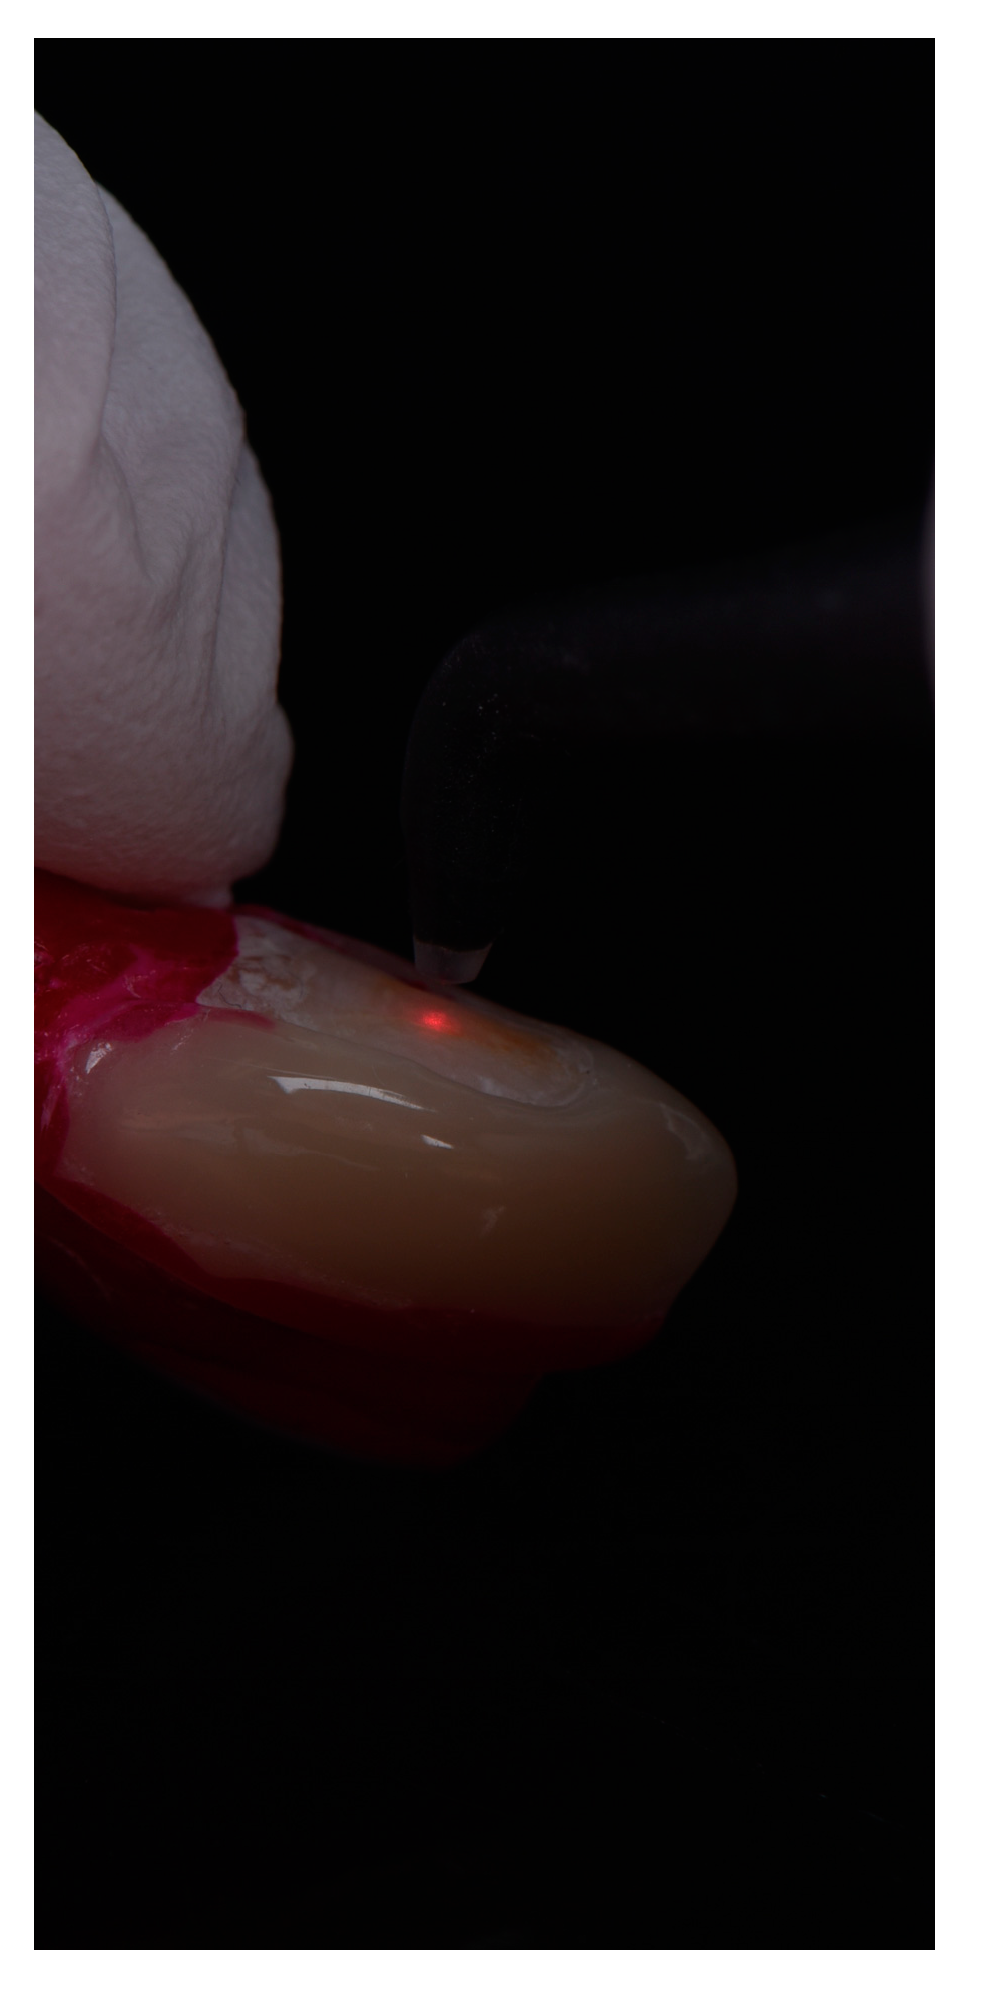

2.3. Radiological and Fluorescence Examination